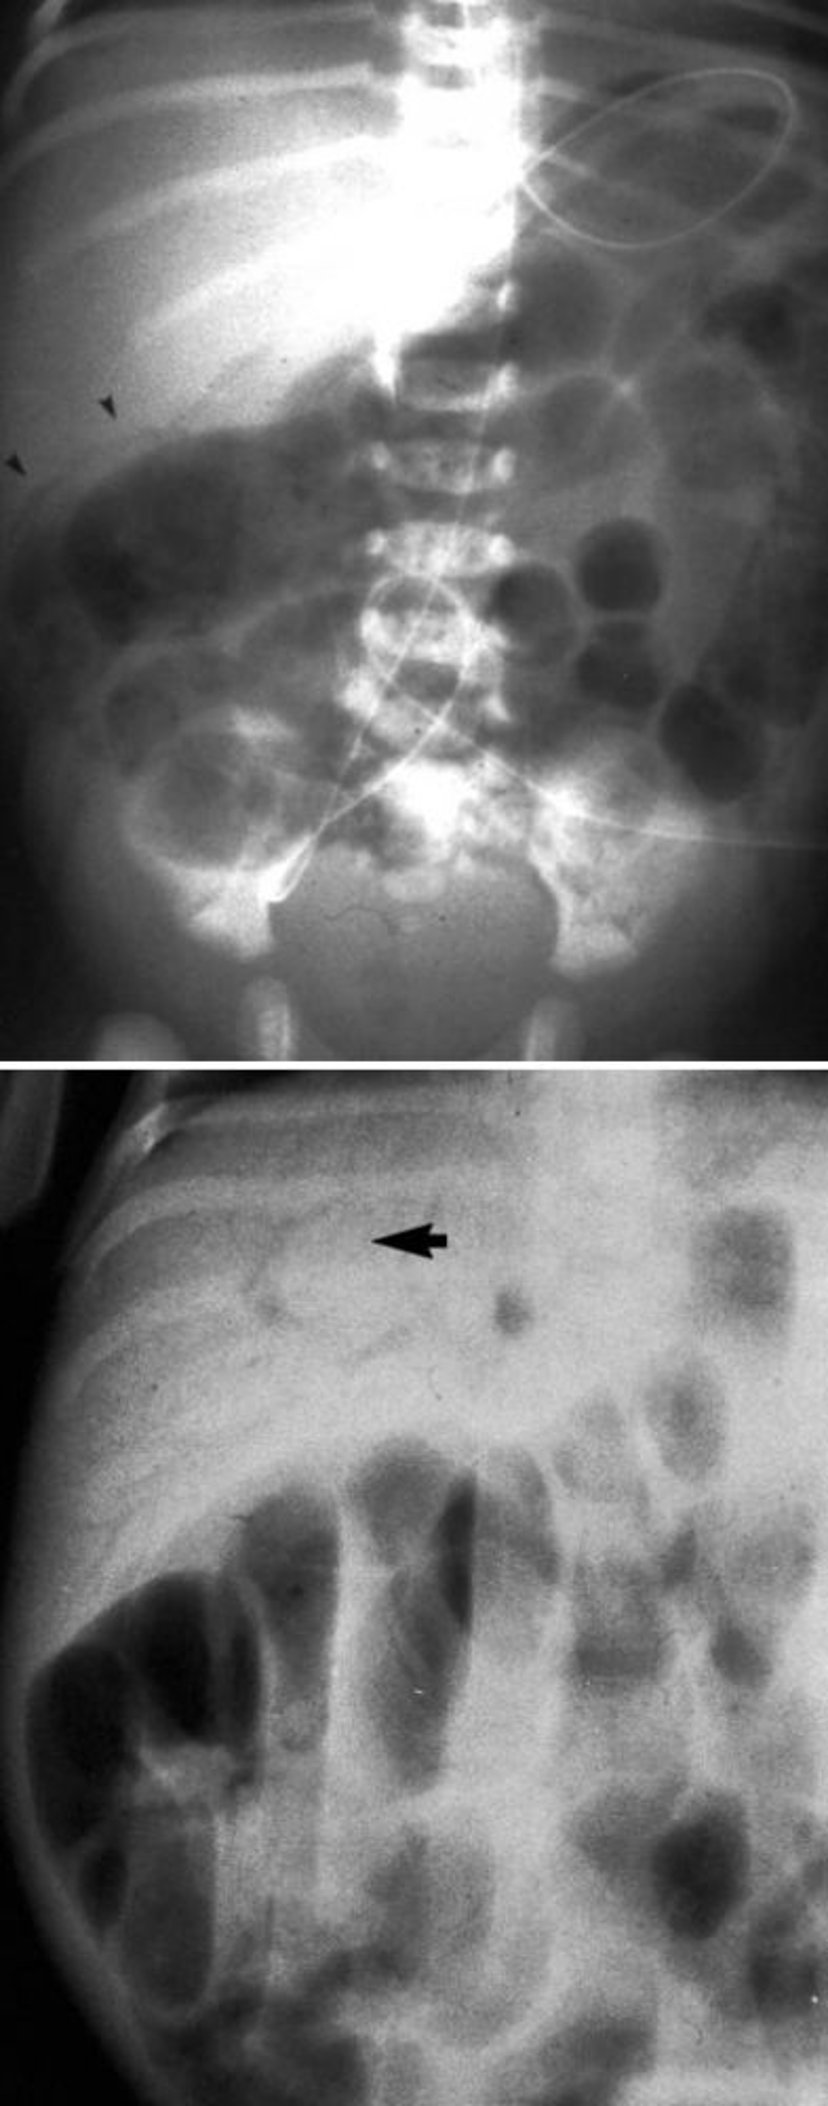

Caratteristiche radiologiche dell'enterocolite necrotizzante

Questa immagine mostra la pneumatosi intestinale (in alto, punte di freccia) e il gas della vena porta (in basso, freccia).